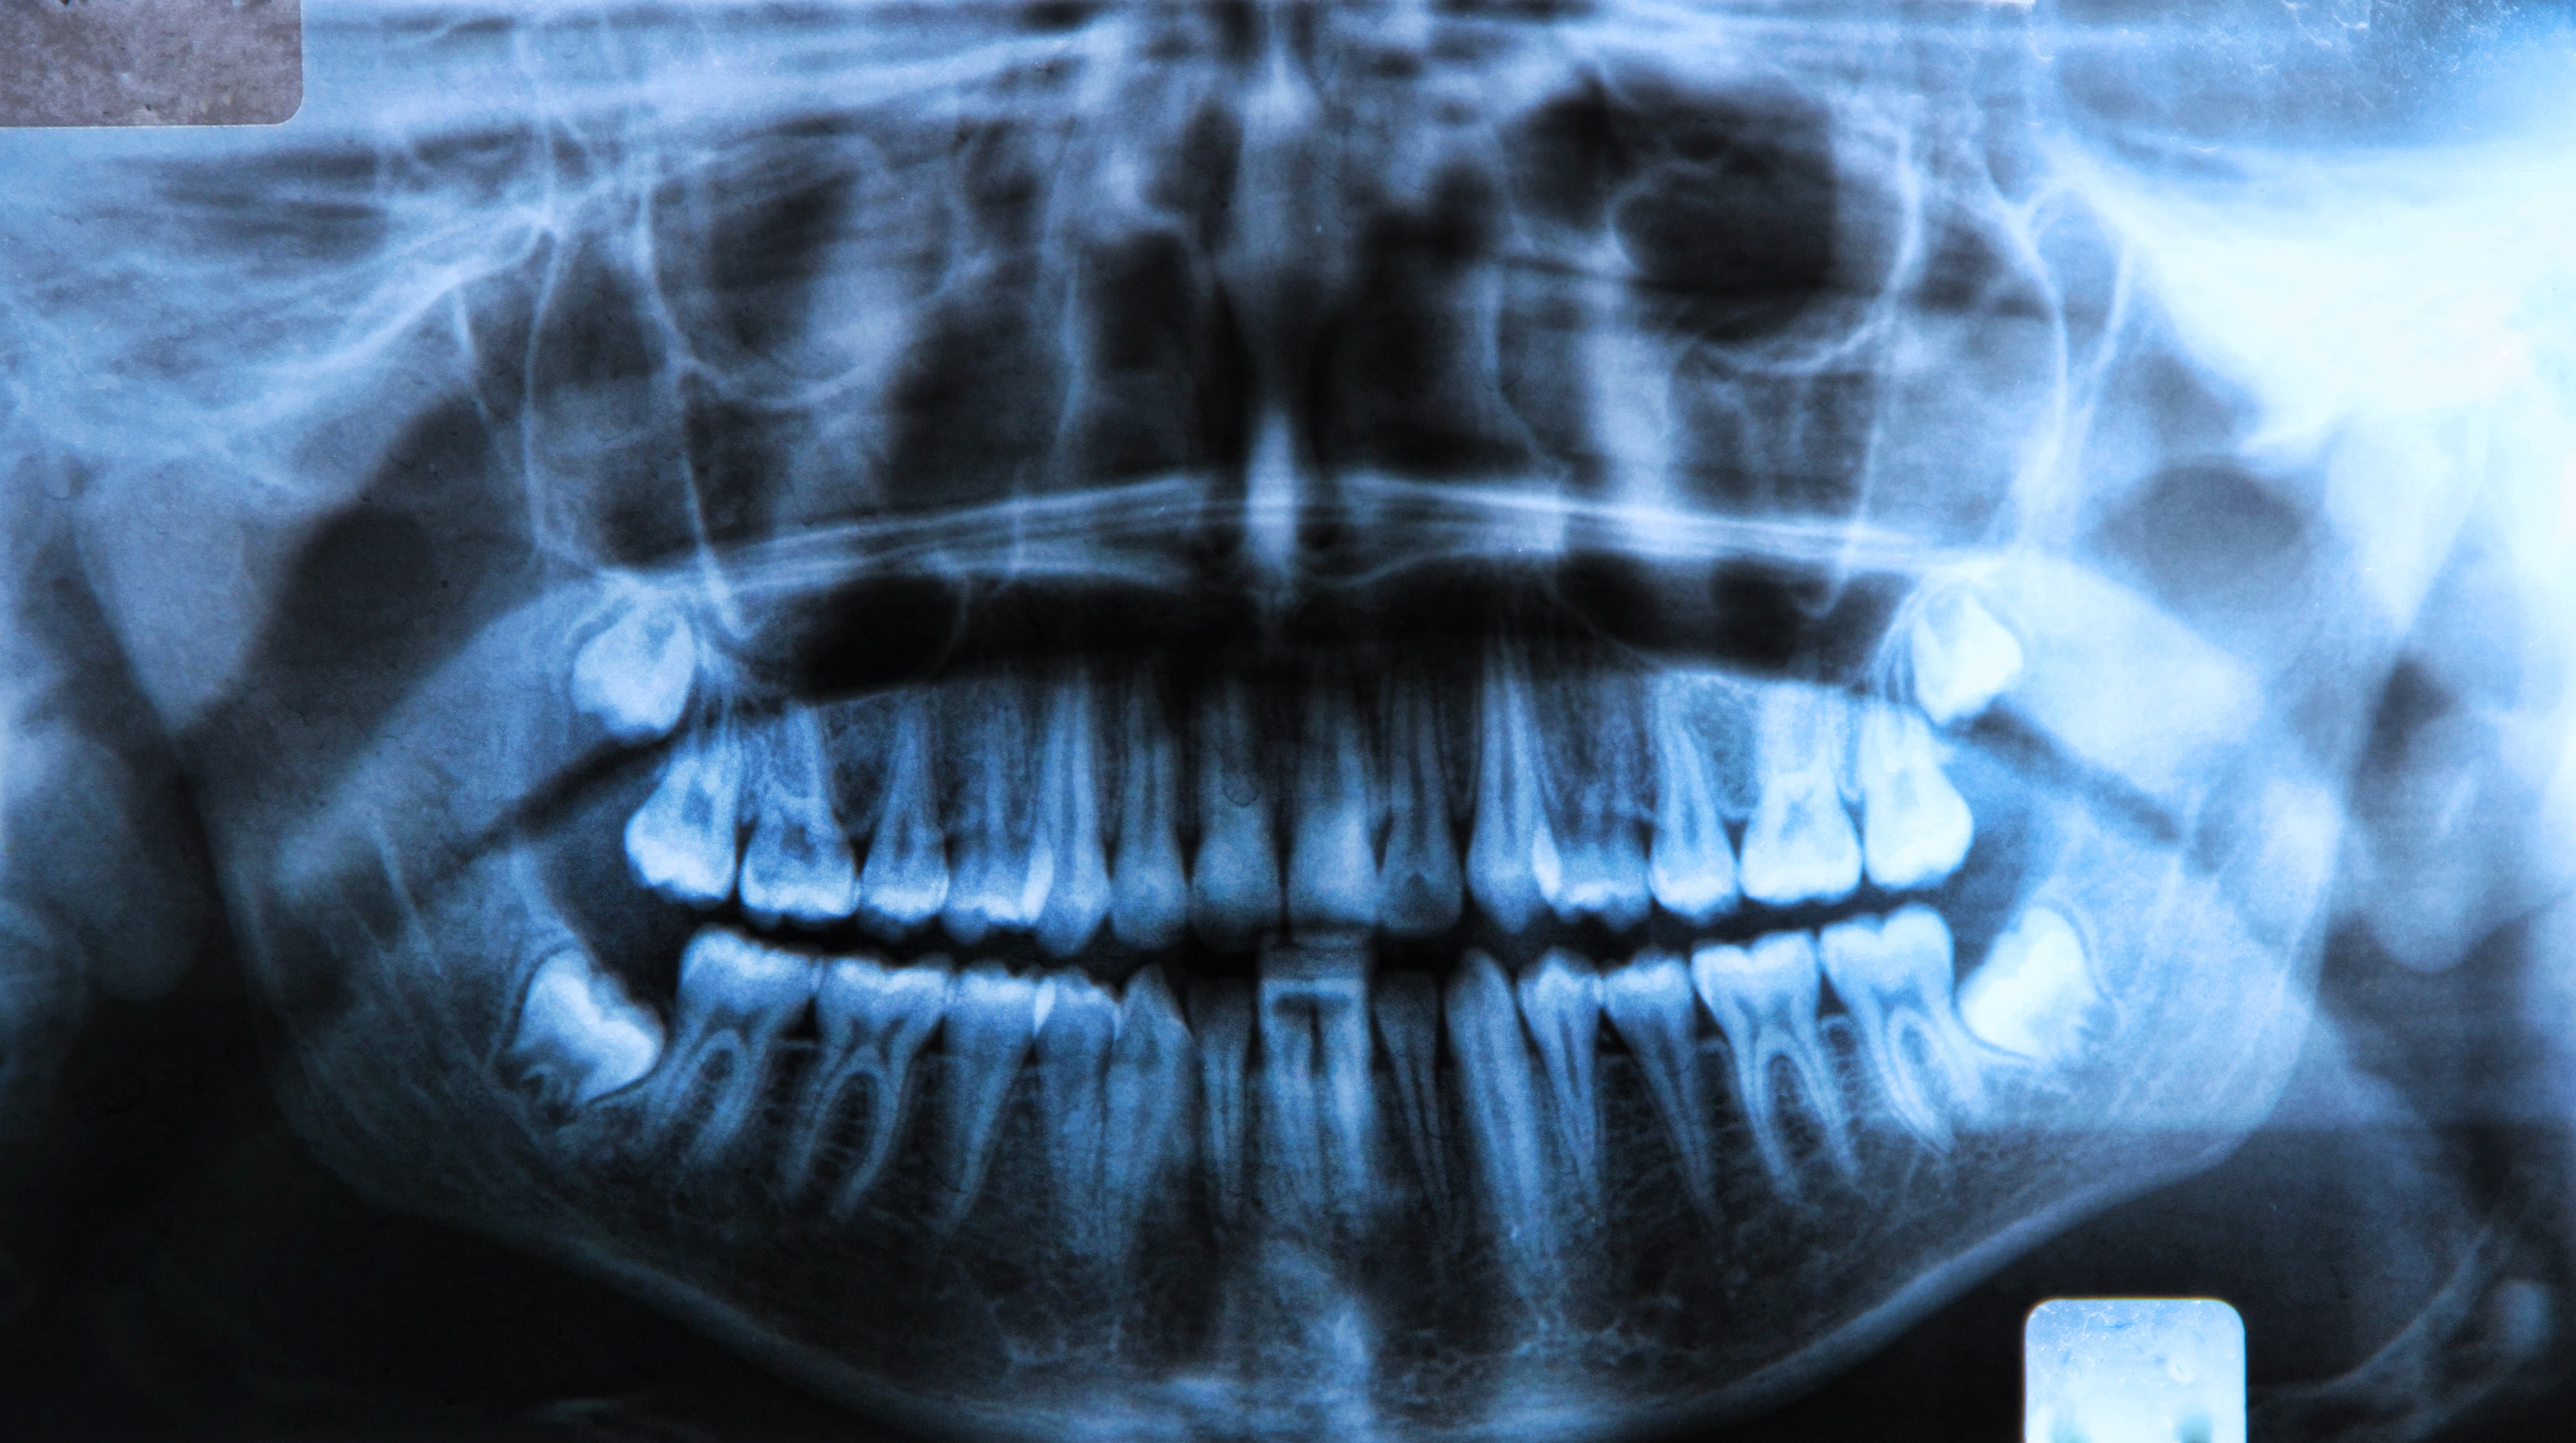

what to expect during wisdom teeth extractions

Wisdom teeth extraction in Edmonton is a common procedure to prevent future dental problems and complications. Common as it is for dentists, we understand that it’ll only happen once for you and that it may feel stressful. The staff at our dental clinic near you will provide detailed instructions about the procedure and how to ensure a full and quick recovery, but it might be a lot to take in. Here’s an additional guide to what to expect relating to wisdom tooth extraction.